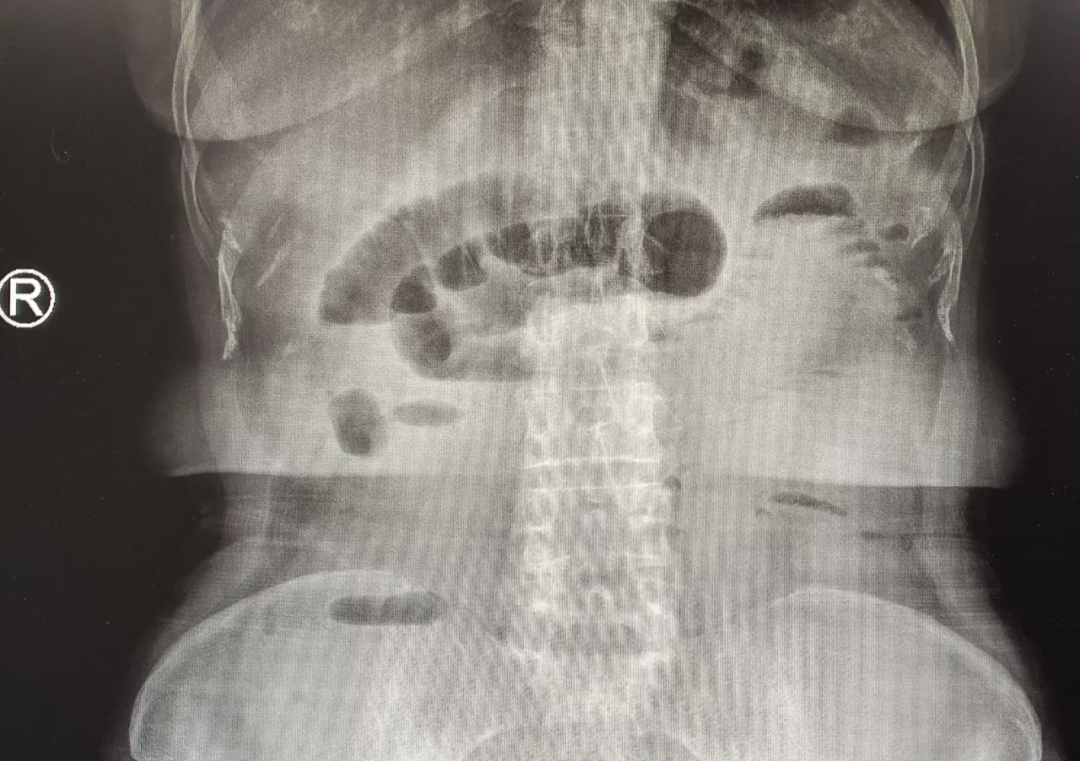

【医线直击】生命通道的守护者——一场与时间赛跑的肠梗阻救治纪实